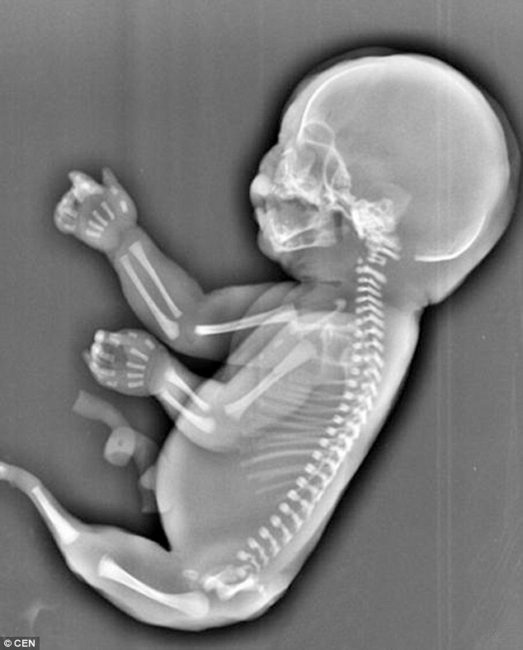

Οι γιατροί διέγνωσαν το έμβρυο με σειρηνομελία ή αλλιώς γνωστό ως «Σύνδρομο της Γοργόνας». Η σειρηνομελία είναι μια σπάνια μορφή δυσπλασίας κατά την οποία τα πόδια αναπτύσσονται συγχωνευμένα.

Οι αιτίες της σειρηνομελίας είναι ακόμα άγνωστες. Η σπάνια πάθηση συμβαίνει μία φορά στις 100.000 εγκυμοσύνες.